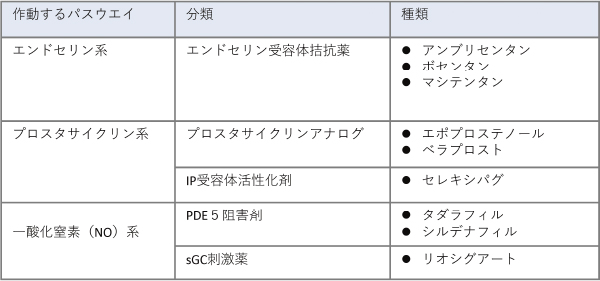

肺高血圧の治療

肺高血圧症には薬物治療と非薬物治療があります。薬物治療には以下のようなものがあります。